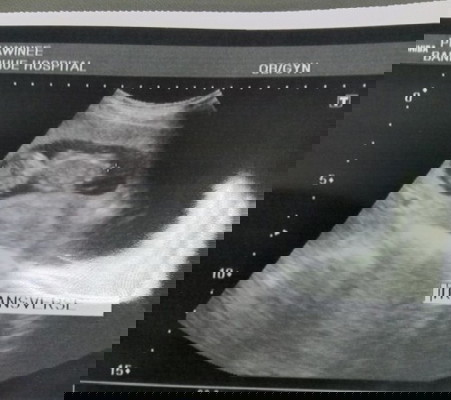

เห็นโพสต์แม่ๆบางคนแล้วอดกังวลไม่ได้เลยค่ะ กลัวท้องลม ตลอดระยะเวลาที่รู้ว่าตั้งครรภ์มาจนถึง 3 เดือน ไม่เคยไปซาวเองที่คลีนิคเลย เพราะเลิกงานไม่ทันคลีนิคซักที 🤣 (เคยซาวตอน 4 วีคที่โรงพยาบาลตอนนั้นเห็นแค่ถุง) วันนี้คุณหมอนัดและอัลตร้าซาวด์ให้ น้ำตาแม่ไหลอาบหน้าเลยค่ะ ดีใจสุดๆ #ลูกคนคนแรก #12week 4days #ทีมมิถุนา65

ลูกชายคนแรก